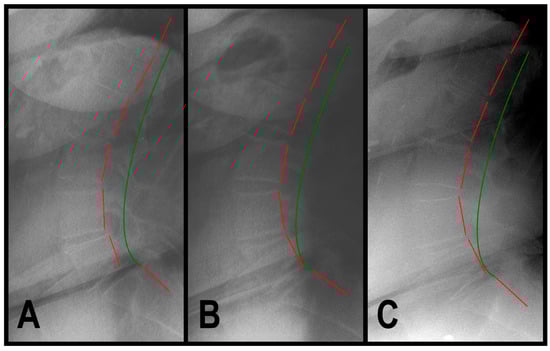

3.1.1. Patient 1

| ARA L1-L5 (°) | −40 | −47.8 | −41.1 | −43.4 | |

| Tz L5-S1 (mm) | 0 | 15.8 | 4.2 | 4.3 | |